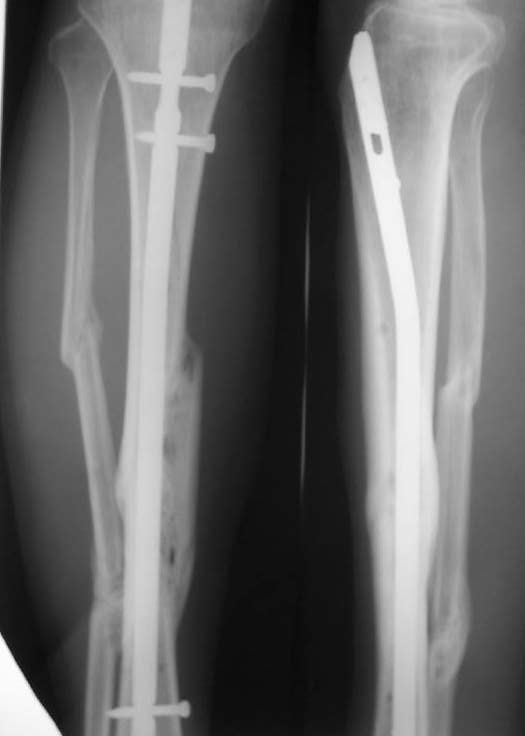

При невозможности или чрезмерной травматичности одномоментного восстановления длины можно пойти двухэтапно (аппарат, потом гвоздь). Похожий пример см. тут. Прошло уже года полтора после остеосинтеза. Может, коллега Зырянов покажет годичный результат, если есть?

Александр Николаевич, к сожалению больной не является на контрольные осмотры. Я последний раз видел больного, когда прошло 7 месяцев после операции БОС. У него все хорошо. Каких либо жалоб и ограничений в нагрузке нет. Высылаю снимки до операции и последние снимки.